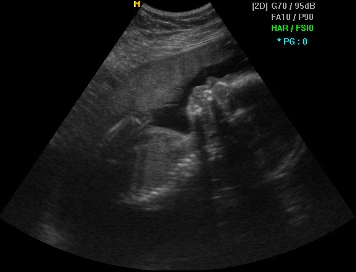

Ембрионот во најраните фази на бременоста